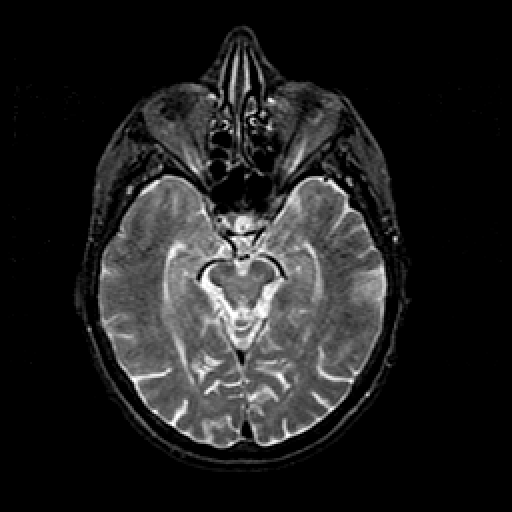

T2-weighted structural MR: Slice 21

Slice 21